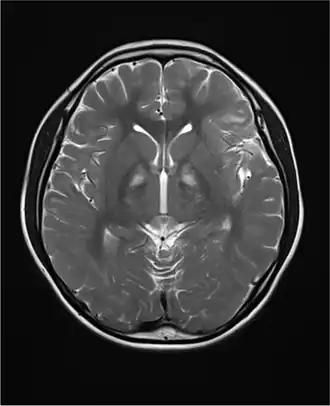

Церебральная фолатная недостаточность

У пациентов с синдромом Кернса — Сейра очень часто обнаруживается церебральная фолатная недостаточность — синдром, при котором уровни 5-MTHF в спинномозговой жидкости снижены, несмотря на нормальные уровни фолиевой кислоты и 5-MTHF в плазме крови[12]. Назначение фолиновой кислоты может в некоторых случаях облегчить симптомы недостаточности и даже скорректировать наблюдаемые на снимках мозга отклонения, особенно если терапия была начата на ранних стадиях заболевания[13]. Предполагаемая причина церебральной фолатной недостаточности у пациентов с синдрмом Кернса-Сейра — дисфункция сосудистого сплетения, нарушающая поступление фолатов в спинномозговую жидкость[14].